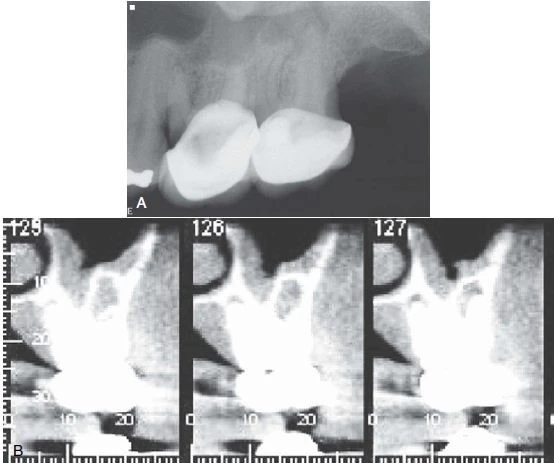

Hình 7. A. Phim X quang hai chiều cho thấy sâu tái phát dưới bờ gần của răng cối lớn thứ nhất hàm trên. Tuy nhiên, bệnh nhân đau khu trú khi nhai ở răng cối lớn thứ hai hàm trên. B. Phim CBCT cho thấy áp xe quanh chóp liên quan đến răng cối lớn thứ hai hàm trên. Hình ảnh mất xương bị hình ảnh xoang hàm trên, xương gò má và xương vỏ chồng lên.